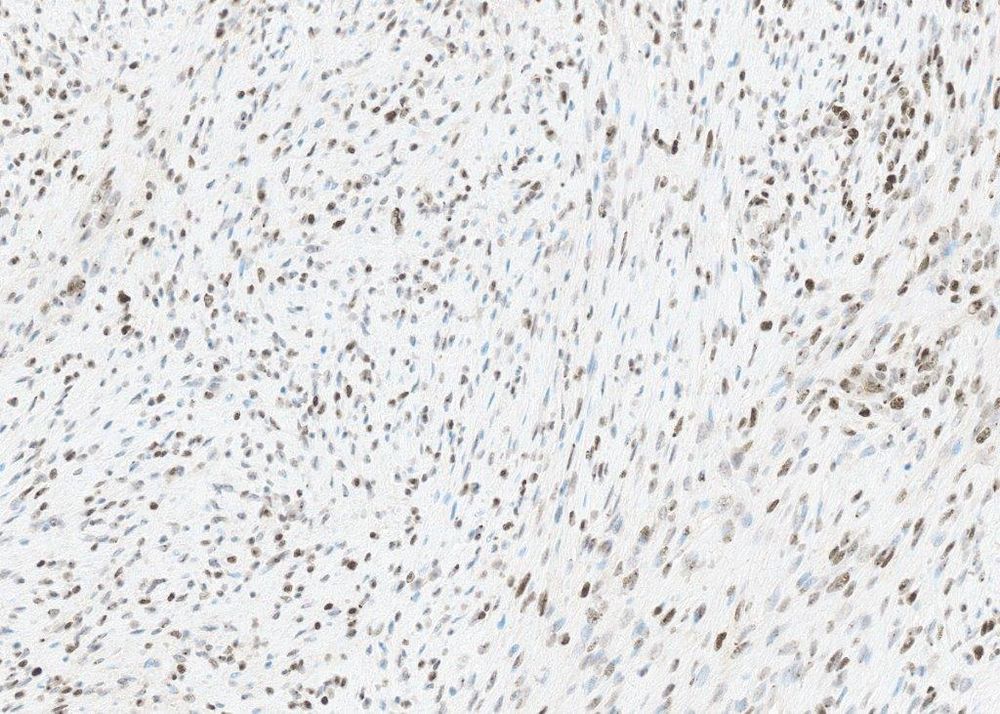

There is a single case report of a desmoid occurring in a Li-Fraumeni patient, with identical morphology. p53 IHC done on this case shows a null/mutated pattern.

May 30, 2025 at 5:36 PM

Fear not. It’s also got these really bizarre cells, all over the place. Those don’t belong in a desmoid! Not a desmoid? Or is there another explanation?

May 30, 2025 at 5:33 PM

#PathSky Abdominal wall mass, middle aged woman. Women basically only get 3 abdominal wall tumors, so it’s got to be a desmoid, DFSP or endometriosis. Classic desmoid morphology, aberrant nuclear beta-catenin. I can hear the cries of “boring..”